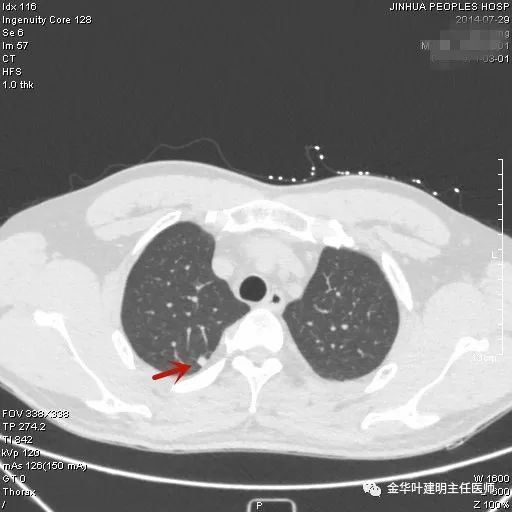

上图示结核。我们发现其有明显的卫星灶,如绿色箭头所示,主病灶处也是周边有模糊区域,病灶整体密度较为均匀(肿瘤容易生长不均致密度欠均匀,显杂乱)。